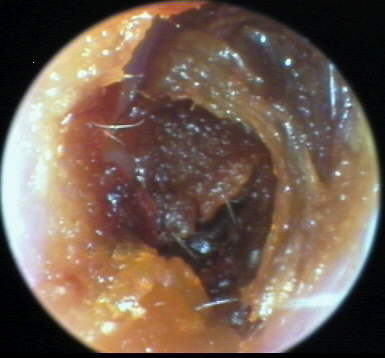

+3: Occlusive major amount present; likely to interfere with insert and circumaural hearing testing, may add a conductive overlay; obstruct hearing aid receiver and vent, reducing effective gain and output. Tympanic membrane not visualized. Removal essential. EXAMPLES:+3/A(25k) | +3/B(27k) | +3/C(27k) | +3/D(17k) | +3/E(19k) | +3F(18k)